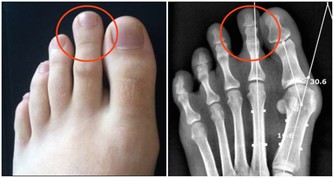

▼原來這個症狀被稱做「乾性溺水」,當水快吸進肺部時,身體會出現保護機制,

造成喉痙攣,導致呼吸能力受影響及昏迷、疲憊、咳嗽及胸口疼痛等。

這樣的症狀發生時,不一定是大量的水才會造成,

有時候只是微量的水就會導致危險發生,即使一開始反應正常,

但一小時之內就有可能因為水進入肺部而導致死亡。